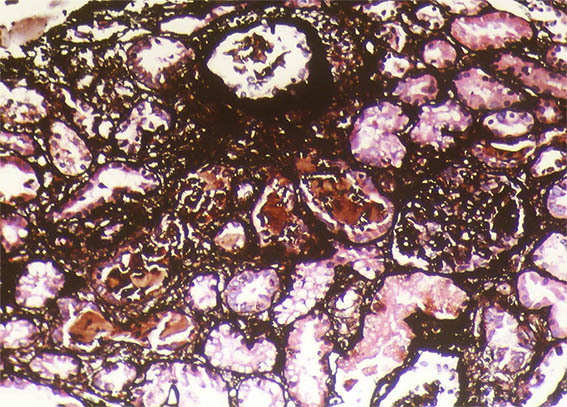

A 40-year-old man presented with severe acute liver failure secondary to hepatitis A virus infection, and acute kidney injury.

More relevant laboratory tests: thrombocytopenia (76,000), hyperbilirubinemia (7.1 mg/dL), transaminitis (1.830 U/L and 2.320 U/L), and elevated INR. Serum creatinine: 5.2 mg/dL, BUN: 78 mg/dL, proteinuria: 100 mg/dL, without microhematuria.

A kidney biopsy was performed. Look at the images.

Figure 11. Methenamine-silver stain, X200.